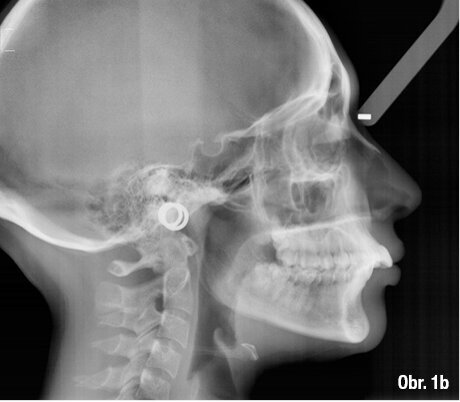

25letá pacientka požadovala estetickou ortodontickou léčbu, kterou nebylo jednoduché naplánovat vzhledem k tomu, že je umělkyní a cestuje po celé Evropě. Během vyšetření byla diagnostikována II. třída 1. oddělení, mírné stěsnání v dolní čelisti a středně těžké stěsnání v čelisti horní. Incizální schůdek byl 10 mm. Profilová zkouška jasně ukazuje protruzní postavení rtů (obr. 1a–c). Pacientka odmítla extrakční nebo ortodonticko-chirurgickou léčbu. Vhledem k jejím požadavkům na estetiku byl léčebný plán stanoven takto: léčba fóliovými aparáty Invisalign (Align Technology) s výsledným postavením molárů i špičáků v I. třídě, které bude dosaženo postupnou distalizací horních molárů s pomocí kompozitních attachmentů na všech distalizovaných zubech a tahů II. třídy (obr. 2, 3). Pacientce bylo doporučeno nosit fólie a tahy II. třídy nejméně 21 hodin denně. Dále pacientka používala přístroj AcceleDent 20 minut denně po celou dobu trvání ortodontické léčby. Fólie byly měněny každé 2 týdny, dokud nebyly druhé horní moláry plně distalizovány, potom každých 10 dnů, dokud nebyly první moláry ve své finální pozici, a nakonec každých sedm dní až do konce léčby.

ClinCheck (Align Technology) software navrhl k získání požadovaných výsledků 63 alignerů s předepsaným množstvím atachmentů a nasazením tahů II. třídy. Odhadovaná doba léčby byla přibližně 30 měsíců. Nicméně protože se pacientka rozhodla používat přístroj AcceleDent, léčba byla ukončena již po 18 měsících bez nutnosti refinementu, tedy s původně plánovanými 63 alignery (obr. 4a–c, 5a–c).

Klinický výsledek byl vynikající, postavení molárů i špičáků v I. třídě, vyhovující překus a předkus. I profil dolní třetiny obličeje byl výrazně lepší.

Na překrytí kefalometrických snímků je zřejmá distalizace molárů o 6 mm bez výraznějšího sklonu a s ideálním bukolingválním sklonem řezáků. Tahy druhé třídy umožnily protrakci mandibuly o 1,5 mm. Jako retenční aparáty jsme zvolili Vivera retainery (Align Technology) (obr. 6, 7a–c, 8a–c).